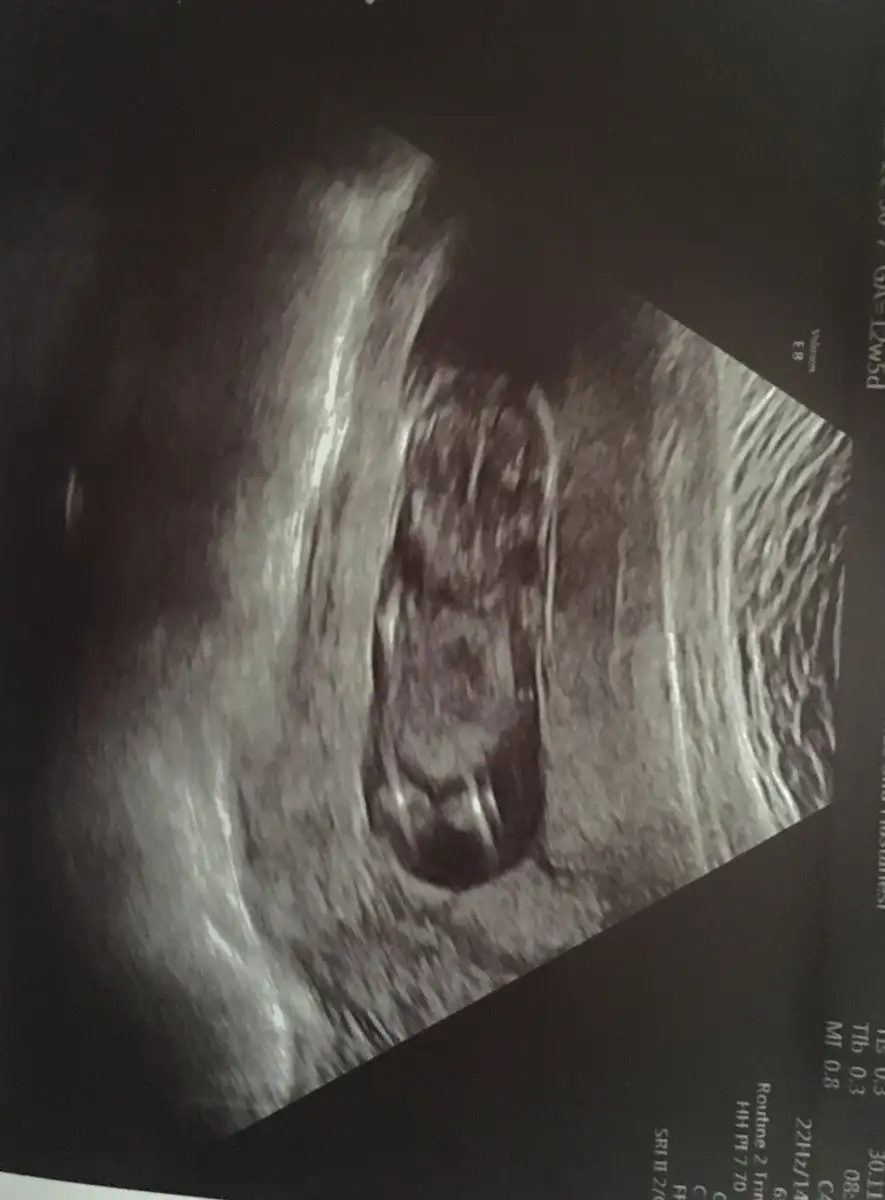

Erkek olsa belli olurdu bence yokki gözükmüyor bende ekledim şimdi bir bacak arası resmi olsa gözükür yanı demekki yoook :))

Böyle alttan goruntusunu hep gosterdı ordan da bakıyordu cınsıyet degılde dr bıseyler olcup dınlıyor ben cınsıyet anlamaya calısıyorum tabı ama doktor bana bacak arasından degıl baska bıyerden anlıyorz dedı

Burdan bısey gozukmuyor ama yandan nasıl yokmu ayrıntılı da alttan gosterdımı benım gbı ordam gordun ku